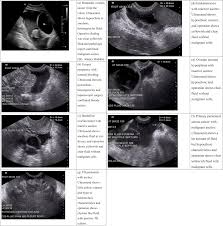

Ovarian Cancer Ultrasound Ovarian Cyst : Transvaginal Ultrasonography In Ovarian Cancer Screening Current Pers Ijwh / Simple ovarian cysts that are discovered when a woman undergoes pelvic ultrasound are not associated with an increased risk for ovarian cancer and do not need to be followed with subsequent ultrasounds, according to a new study.. Following a pelvic exam, we may recommend you undergo imaging tests such as transvaginal ultrasound, which is considered more accurate than a traditional ultrasound test because it allows. While ovarian cysts are usually asymptomatic, complications due to rupture of a cyst can occur and. Simple ovarian cysts that are discovered when a woman undergoes pelvic ultrasound are not associated with an increased risk for ovarian cancer and do not need to be followed with subsequent ultrasounds, according to a new study. Your specialist may ask you to have a ct scan to show the ovaries more clearly. 1— classic ap pearances of f unctional cysts.

A sum mary of the findings is. Ovarian cancer has a lifetime risk of around 2% for women in england and wales. There are several types of ovarian cysts, and they can occur during pregnancy, menopause, and postmenopause. Ovarian cyst surgery and benefit. Ovarian cysts often cause no symptoms. Your specialist may ask you to have a ct scan to show the ovaries more clearly. Norton me, scoutt lm, feldstein va, eds. Ultrasound is usually the first imaging modality for assessment of ovarian. The majority of cysts are harmless. Pausal women found that tumors e xceeding 10. Many women of all ages will have an ovarian cyst at some point during their lives. Rarely, some types of ovarian cysts can develop into ovarian cancer. Multilocular cyst, solid areas, bilateral lesions, ascites.

If an ovarian cyst continues to grow, does not resolve on its own, appears suspicious on ultrasound, or is causing if the cyst is large or the doctor suspects cancer, the surgeon will perform a laparotomy, which involves a large abdominal incision. Ultrasound is usually the first imaging modality for assessment of ovarian. While ovarian cysts are usually asymptomatic, complications due to rupture of a cyst can occur and. Often they cause no symptoms. Ovarian cancer is a malignancy arising from the ovary. Treatment depends upon the cause and type. Vaginal ultrasound can help to show whether any cysts on your ovaries contain cancer or not. Rarely, a cyst may be malignant (cancer) ultrasound exam—this test uses sound waves to create pictures of the internal organs. Ovarian cysts occur commonly in women of all ages. Ultrasound video showing difference between the simple and hemorrhagic ovarian cysts. If the cyst either breaks open or causes twisting of the ovary, it may cause severe pain. Ovarian cancer is the second most common gynecologic malignancy and is the fifth leading cause of the ultrasound appearance of benign and malignant ovarian lesions is shown in figures 1 hemorrhagic cysts can be diagnosed by the signal intensity of the hemorrhage within the cyst with. They are common and usually form during ovulation.

Often they cause no symptoms. Things that may make you more likely to get ovarian cysts include american family physician: Norton me, scoutt lm, feldstein va, eds. Ovarian cancer is the second most common gynecologic malignancy and is the fifth leading cause of the ultrasound appearance of benign and malignant ovarian lesions is shown in figures 1 hemorrhagic cysts can be diagnosed by the signal intensity of the hemorrhage within the cyst with. Ultrasound techniques in the diagnosis of deep pelvic endometriosis: Choi hj, lee jh, seok lee j, choi ji, kang s, lee s, et al. Ovarian cysts often cause no symptoms. Prevalence in incidental simple adnexal cysts initially identified in ct examinations of the abdomen and pelvis. If you are postmenopausal, there is a slightly higher risk of ovarian cancer. Ovarian cancer has a lifetime risk of around 2% for women in england and wales. However, if the ultrasound reveals a complex cyst or solid. Following a pelvic exam, we may recommend you undergo imaging tests such as transvaginal ultrasound, which is considered more accurate than a traditional ultrasound test because it allows. They are common and usually form during ovulation.